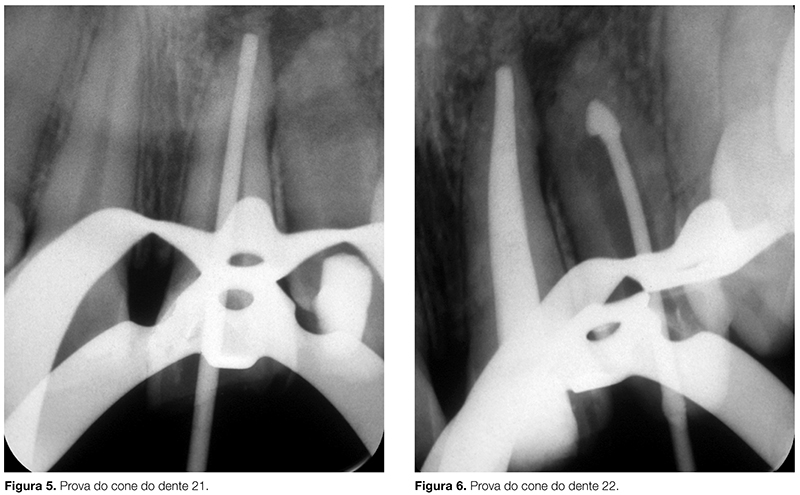

Em 20 de março de 1999, um ano e dois meses após o início do tratamento endodôntico, foi realizada a obturação definitiva do canal por meio de cones de guta-percha (Fig. 5, 6) e cimento obturador à base de óxido de zinco e eugenol (Endofill, Dentsply), por meio da técnica de condensação lateral seguida de condensação vertical (Fig. 7).